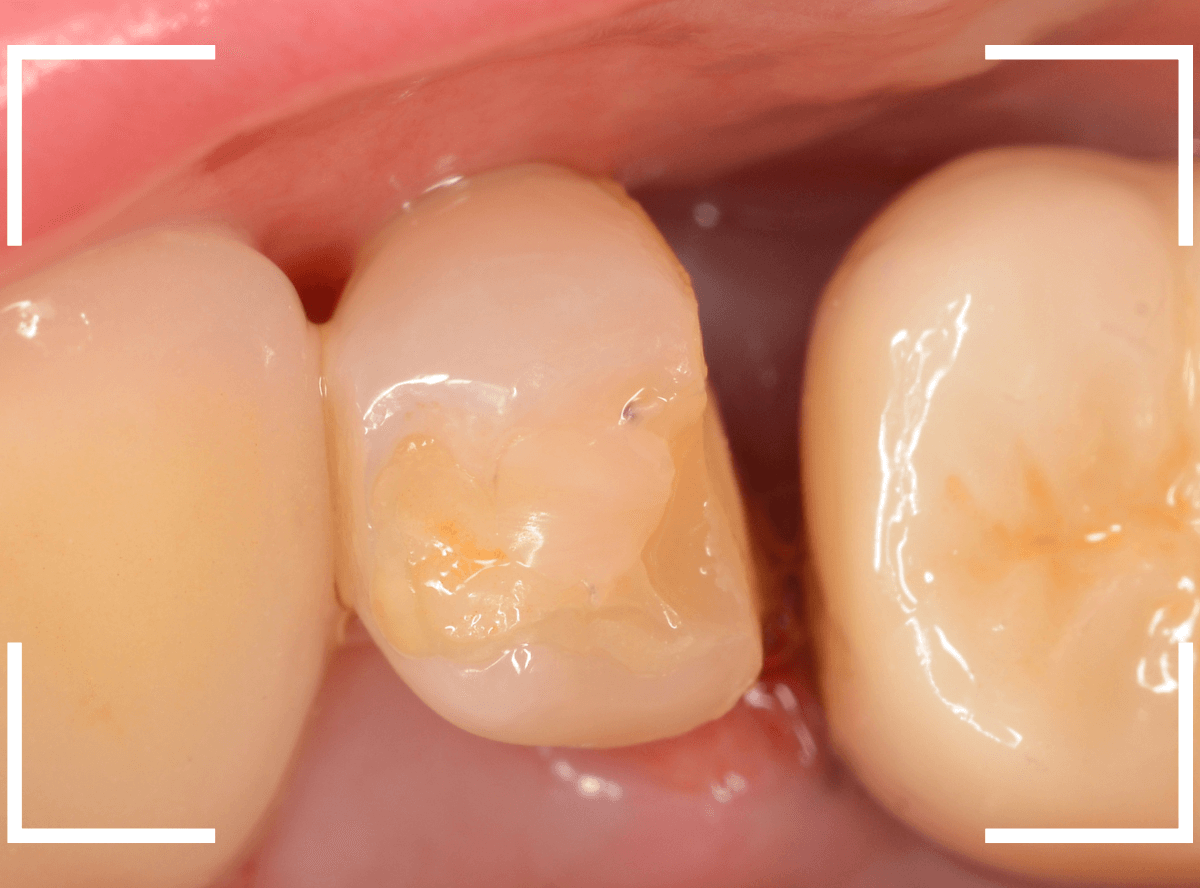

まず、CAD/CAM冠を外します。

中のメタルコアも外して再製します。

歯を傷つけないように、時間をかけてそ~っとメタルコアを除去します。

メタルコアを除去して中を調べてみると、うっすらと虫歯になっていました。

このような状況は、入っているものを外してみないとわかりません。

虫歯を一層除去し、型どりします。